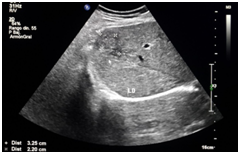

Male patient of 37years of age , white race, resident in Habana del Este municipality of Havana province, with previous health history that comes to consultation for presenting prolonged febrile syndrome with 56days of evolution, febrile peaks of 38‒39 degrees, accompanied by chills and decay. Urinary sepsis was determined as initial diagnosis so antimicrobial treatment was imposed for 10 days. There is no improvement in the clinical picture and the febrile symptoms persist. The patient is admitted to the hospital service of the Central Hospital in Havana. On physical examination, painful abdomen on palpation in the right hypochondrium and epigastrium without other alterations Laboratory tests are performed or presenting Haemoglobin: 12gl, Leucogram which yields an Eosonophilia of 66% and an Erythrosedimentation: 67. Serial blood cultures and urine cultures they were negative. Likewise, the serology was negative. Within imaging studies abdominal ultrasound reporting hepatomegaly that exceeds be 2 cm costal margin with the presence of a hypo echoic image with nodular, peripheral tendency without flow Doppler level right lobe study (Figure 1) interpreting c indicated omo pyogenic liver abscess therefore imposes treatment with antimicrobial therapy (Metronidazol EV) (Figure 1). Ultrasound: nodular, hypoechoechoic, peripheral, non‒vascularised image at the level of the right lobe of the liver clinically the patient improved his general condition, but he kept the febrile syndrome accompanied by diffuse abdominal pain. By keeping the same ultrasound image last month of treatment study it was conducted by T omografía who reported abdominal the presence of density areas of irregular appearance, in the right lobe of the liver in segments VII and VIII and endovenous study showed lesions with poor contrast capitation both Portal and late phase (Figure 2). Computed tomography with intravenous contrast: hypo dense areas of irregular appearance at the level of segments VII and VIII of the liver with poor contrast uptake Ultrasound images suggested the diagnosis of parasitosis Fasciola hepatica but also by positron raised the differential diagnosis of Focal nodular hyperplasia at que sugi river echo directed FNA that reported cytological Negative of neoplastic cells and inflammatory infiltrate with abundant eosinophils. Given this possible diagnosis, endoscopy was performed, which reported alkaline pangastropathy with a duodenal swab for negative parasitological study. Conical crown was made on several occasions resulting negative and biliary drainage was indicated to be not useful for diagnosis. In view of Clinical and Imaging suspicion of Fasciola hepatica, it was decided to perform a weekly evaluative ultrasound for 4 more weeks, observing at the end of the fourth week echogenic images, elongated with movements inside the gallbladder and an echogenic image without acoustic shadow in the canal. Coledochus suggesting the diagnostic imaging of adult Fasciola parasites in the bile ducts (Figure 3). Evolutionary ultrasound: echogenic images, free, with movement at the level of the gallbladder. The patient was referred to the Institute of Tropical Medicine (IPK) where the diagnosis was verified, imposing treatment with a single oral dose of Triclabendazole with excellent therapeutic response.

Figure 3 Evolutionary ultrasound.

In hepatic fascioliasis, hypo echoic, anfractuous, well‒defined focal lesions of variable size can be observed, with a tendency to accentuate in 96% of cases (similar to the case reported), although variable echo genicity is also described . However, it is not always possible to visualize the paths that give it the characteristic stamp, so its role in acute Fasciolosis is less. The presence of per portal adenopathies is also described in 74% of cases, although this finding is nonspecific and is present in acute and chronic hepatitis, abdominal neoplasm’s, abdominal tuberculosis and sclerosing cholangitis, among other pathologies.13,14 In Biliary Fascioliasis, the role of ultrasound is greater, given that it is able to confirm parietal thickening of the common bile duct with moderate dilation , although this finding is also seen in pathologies such as sclerosing cholangitis and AIDS cholangitis . More specific is the observation of mobile structures in the gallbladder and / or common bile duct, representing the adult form of Fasciola,14,15 a finding found in the reference patient.